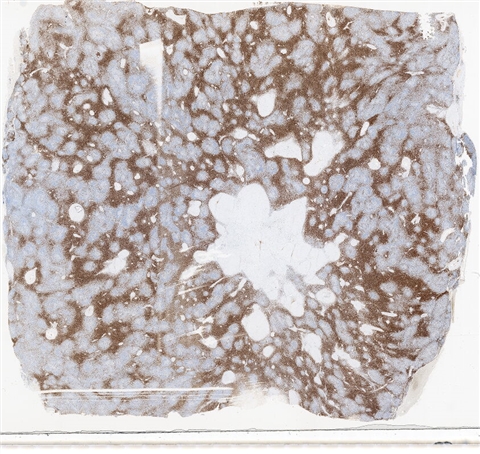

案例3 (6862)

性别:       年龄:65

患者详情: 患者3月余前在当地社区卫生服务中心体检发现血肌酐升高(109.8umo/L),无明显尿量减少,无颜面下肢浮肿无腰酸腰痛,无肉眼血尿,无关节疼痛,无皮疹红斑,开始未重枧及进一步诊治。10余天前患者到中山医院复查生化提示“肌酐200umol/L、尿素7.3mmol/L、尿酸637umol/L、白蛋白34g/L、球蛋白66g/L、蛋白电泳β15.0%、蛋白电泳Y42.6%”,同时其它检查提示“血lgG4 54.20g/L”。 CT:纵隔及双侧腋下多发肿大淋巴结,肺动脉干稍増粗,主动脉硬化,扫及双肾饱满,后腹膜发淋巴结。 PET-T:全身多区域淋巴结肿大、双侧泪腺、双侧颌下腺及胰腺体尾部饱满、双肾实质肿胀,左侧头皮局部增厚,伴FDG代谢增高,鼻咽顶后壁及前列腺腺体FDG代谢增高,上述病灶首先考虑IgG4相关性疾病所致可能,建议暖股沟淋巴结活检病理明确除外淋巴瘤。

大体所见: 结节一枚3*3*2cmA-C。

医院: 上海交通大学医学院附属仁济医院